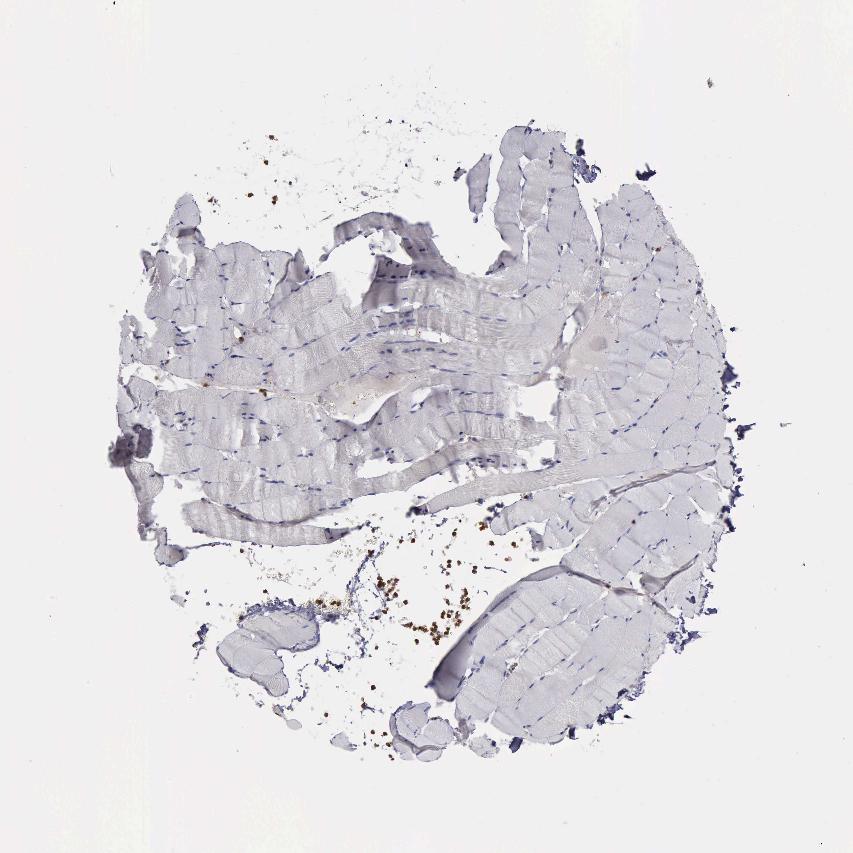

SKELETAL MUSCLE - Antibody stainingi

Antibody staining in the annotated cell types in the current human tissue is reported as not detected, low, medium, or high, based on conventional immunohistochemistry profiling in selected tissues. This score is based on the combination of the staining intensity and fraction of stained cells.

Each image is clickable and will lead to virtual microscopy that enables deeper exploration of all samples and also displays staining intensity scores, fraction scores and subcellular localization as well as patient and tissue information for each sample.

Antibody HPA001115Antibody HPA002925Antibody CAB000356

Myocytes Not detectedNot detectedNot detected